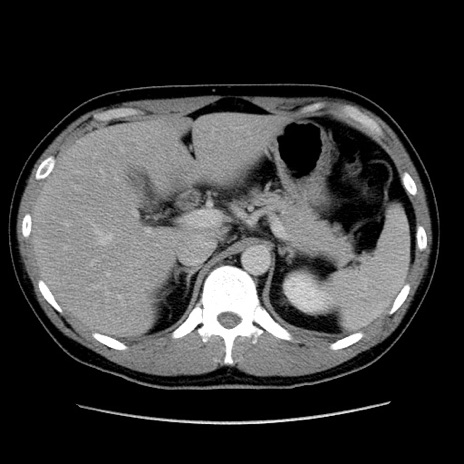

冠状断像

【症例】30歳代男性

【主訴】腹痛、嘔吐

【現病歴】昨晩から突然の腹痛あり、その後嘔吐、軟便も出現。腹痛が改善しないため救急搬送となる。2日前にしめ鯖の食事歴あり。

【身体所見】意識清明、苦悶様、BP 135/90mmHg、BT 35.7℃、腹部:平坦、やや硬、心窩部〜臍部に自発痛、圧痛あり、筋性防御+、反跳痛-

【データ】WBC 8100、CRP 0.57